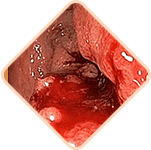

3 Riesgos graves de las hemorroides

Cualquiera de los siguientes

puede ser letal:

Las hemorroides pueden ocultar

enfermedades serias del recto:

- Lesiones

- Hemorragias intestinales

- Cambios necróticos

- Cáncer

Los vasos sanguíneos dilatados en las hemorroides pueden sufrir daños y romperse, aumentando el riesgo de hemorragia. La severidad de la hemorragia puede variar desde leve hasta severa, requiriendo cirugía o incluso transfusiones de sangre.

Las hemorroides crónicas pueden causar la formación de coágulos en los vasos sanguíneos. Con el tiempo, estos coágulos pueden desprenderse y obstruir los vasos de otros órganos internos, causando accidentes cerebrovasculares, embolia pulmonar y tromboembolia coronaria.